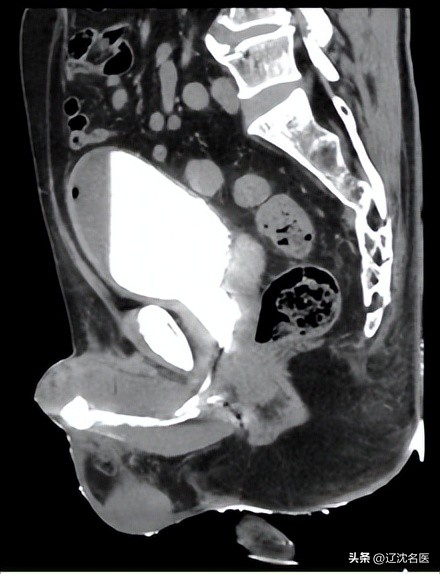

病例1:肾窦肿瘤腹腔镜下解剖性根治术。专家团队成员、中国医科大学附属盛京医院曹志强主任边做边教学。

病例2:复杂后尿道重建术(骨盆骨折,后尿道二次手术),院内首例。上海六院徐月敏老师边做边教学。

病例3:复杂前尿道重建术(长段狭窄,22cm),省内首例。